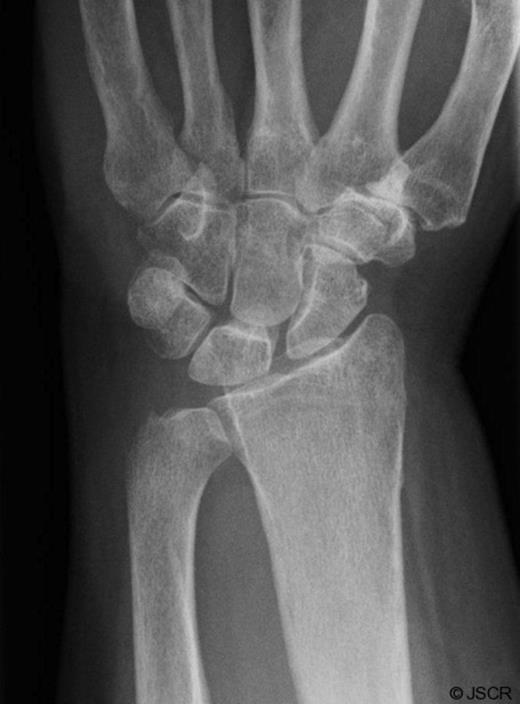

She was subsequently referred to the hand clinic. X ray this time showed destruction of the ulnar styloid consistent with a bony infection (Figure 2). MRI showed destruction localised around the ulnar head with oedematous changes extending up the shaft of the ulna (Figure 3).

MRI showing localised destruction around the ulnar head. The MRI also shows thickening around the extensor carpi ulnaris tendon in keeping with marked tenosynovitis at this site.